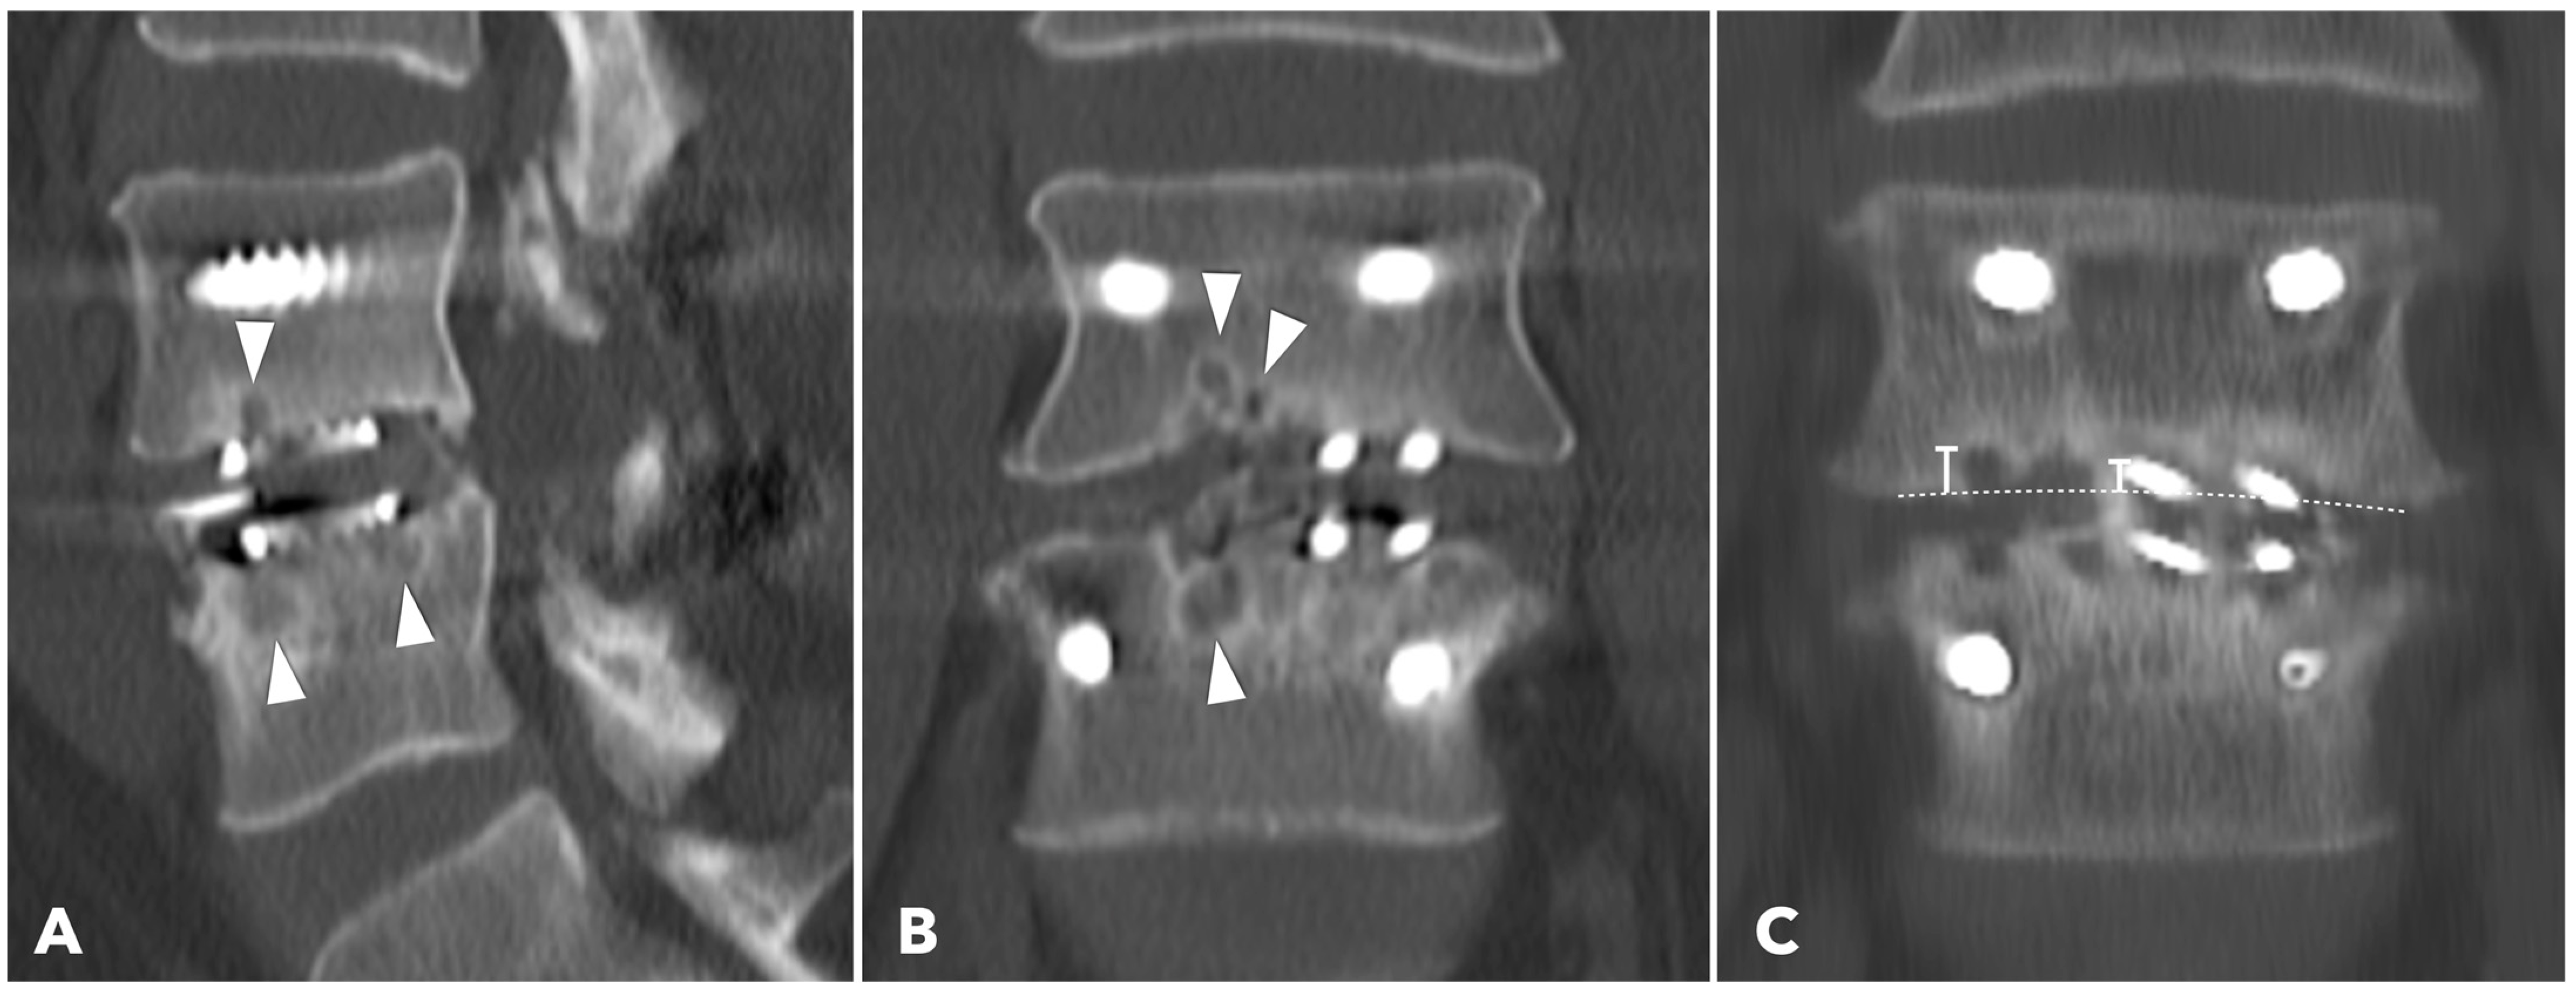

Lumbar spine computed tomography (CT) with 3 mm thin-slice coronal and sagittal reconstructions was performed one year after the surgery. Fusion status was assessed using the Bridwell grading system based on bone window images (Figure 4). Grades I and II were defined as successful fusion. Cage subsidence was defined as sinking > 2 mm beyond the bony endplate [24,30]. The presence of subchondral osteolysis was also recorded as a potential indicator of pseudoarthrosis (Figure 5).

Figure 5. (A,B) 1-year CT reconstruction revealed the presence of subchondral osteolysis or endplate cyst formation (white arrowheads). (C) The measurement of cage subsidence on the coronal CT reconstruction image.

Subchondral osteolysis was significantly more frequent in the MISTLIF group (52.9% vs. 13.3%, q < 0.001). Cage subsidence was also significantly more prevalent in the MISTLIF group (13.7% vs. 5.0%, p = 0.023), although most patients in both groups exhibited no evidence of subsidence (Table 5). Again, the statistical significance was no longer significant after applying the Benjamini–Hochberg correction to control the FDR.